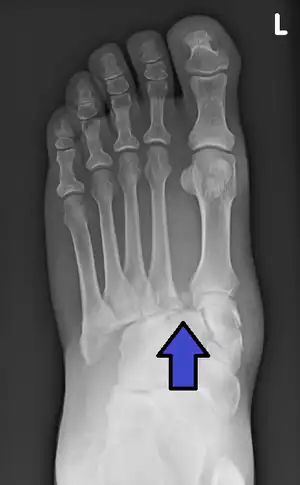

| Jones fracture | Sir Robert Jones | fracture of base of 5th metatarsal extending into intermetatarsal joint | inversion of ankle | Jones fracture Archived 2006-07-02 at the Wayback Machine at Wheeless' Textbook of Orthopaedics online | |